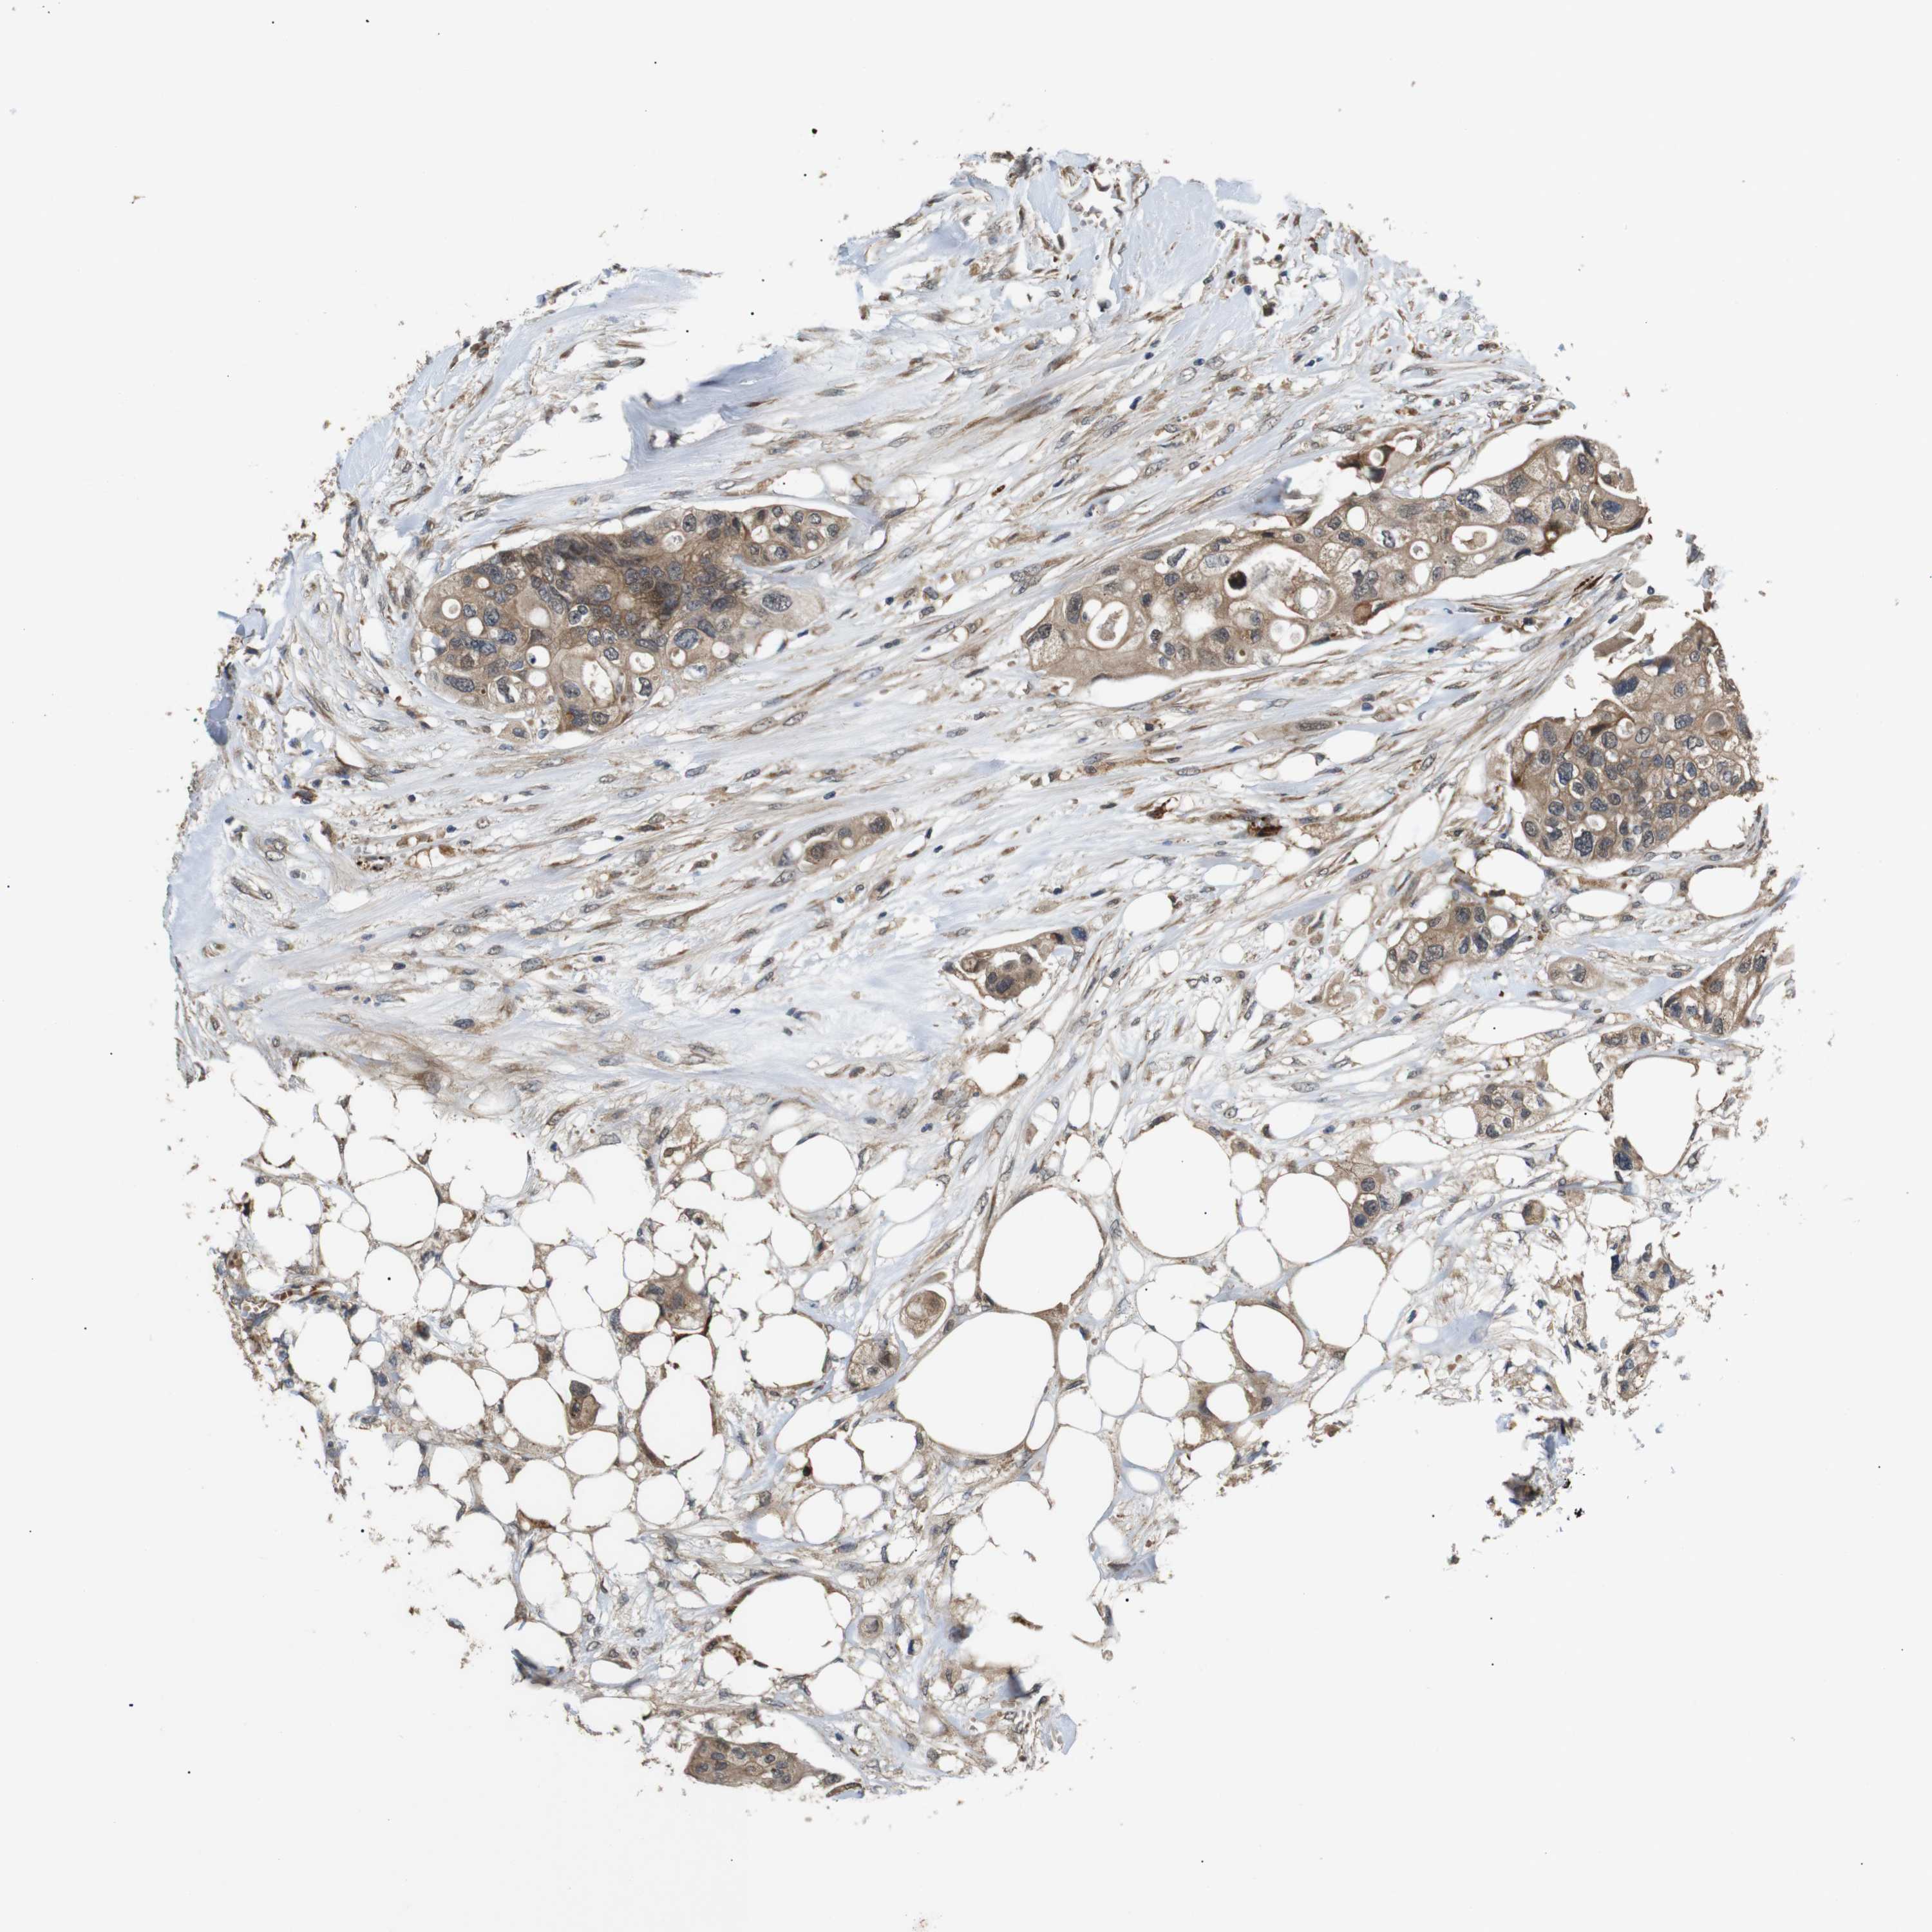

CANCER COLORECTAL CANCER Show tissue menu

Colorectal cancer

Human cancer

Colon adenocarcinoma